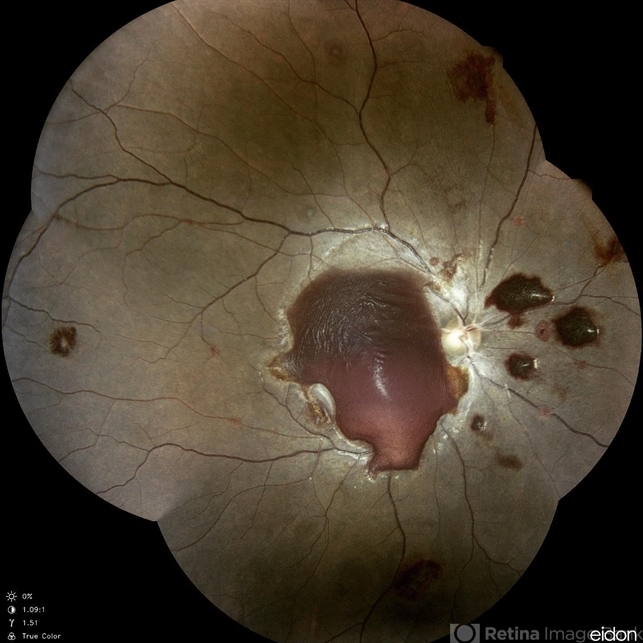

- anaemic retinopathy

- Dr Chinmayi Vyas, Nethradhama superspeciality eye hospital , banglore, india

Scanning laser ophthalmoscope

Eidon fundus imaging - Description

- Anemic retinopathy related retinal hemorrhages in a 24 years old male with Hb of 4.2gm/ dl. The manifestations of anemic retinopathy are nonspecific and may closely simulate hypertensive or diabetic retina. Retinal changes in anemia are cotton wool spots, venous tortuosity, and hemorrhages which may be present at all levels of the retina and choroid. All retinal hemorrhages can occur when Hb falls below 8 g/100 ml or if the platelet count falls below 50,000/cumm. The combination of severe anemia and thrombocytopenia is likely to produce retinal hemorrhages. The Roth’s spots or white centre hemorrhages are typically associated with bacterial endocarditis , anemia and other systemic conditions. The white center is suspected to represents focal ischemia, inflammatory or infectious infiltrate, fibrin or accumulation of neoplasticism cells.